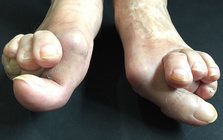

痛みを増し、変形症状、体を支える事が大変になり

歩行の困難、膝や腰などの痛みの発症に。

外反母趾の問題は痛みだけではありません。

その変形症状から多くの身体の不具合と

ほかの症状、病気を発症させてしまう方、

歳を重ねて健康、生活、行動の自由を奪われて

行く方が多いです。